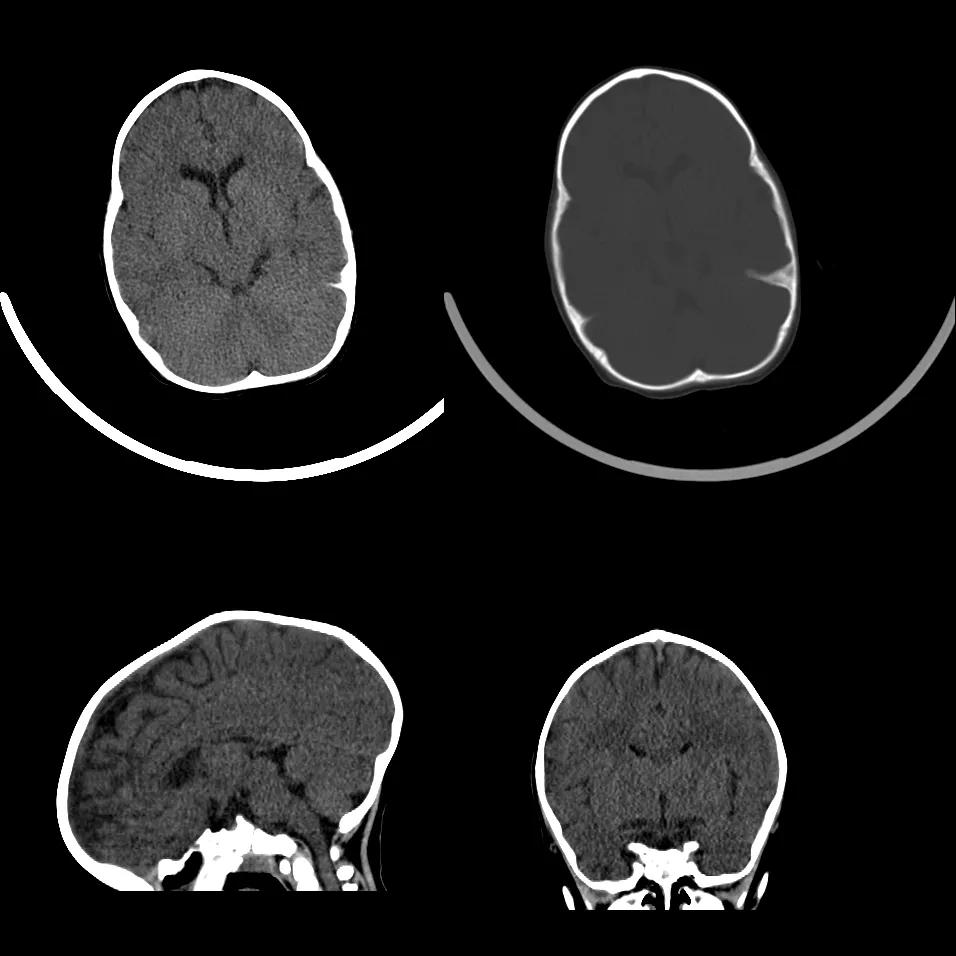

case 1:幼儿男性,1 岁 2 月,出生后发现头颅畸形 1 年余。

诊断:狭颅症。